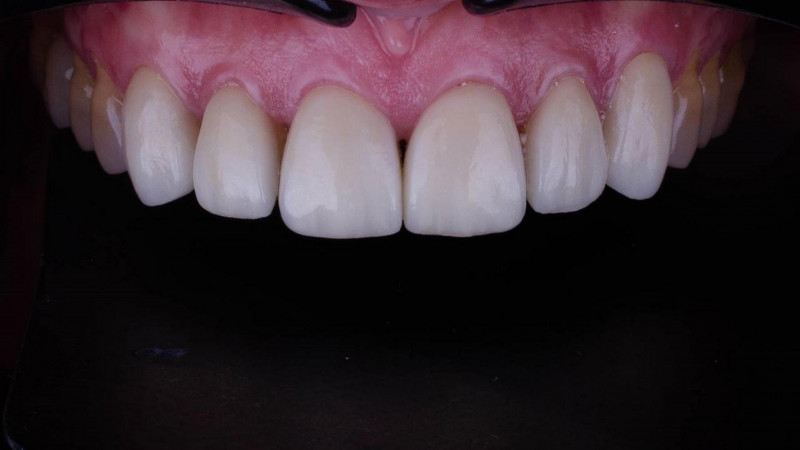

Установка керамической коронки

Все зубы покрыли керамическими винирами и коронками. Установили коронки на имплантаты.